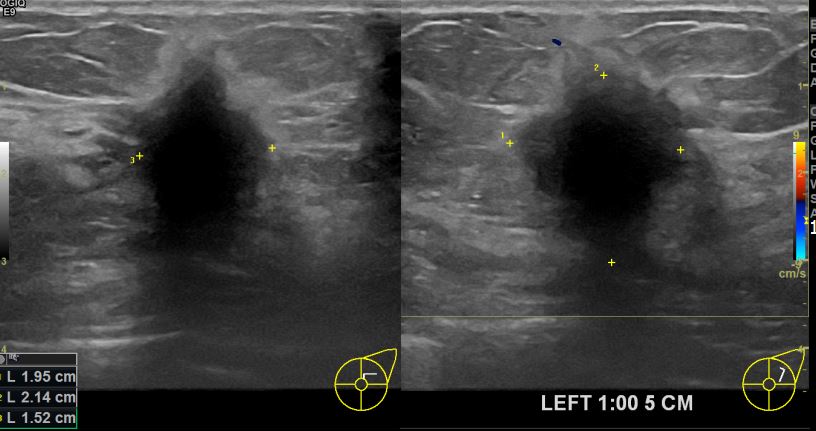

상기환자 타원서 조직검사 권유로 내원하신 60대 여성분으로 의심스러운 좌측의 혹

조직검사진행후 유방암 진단되었읍니다